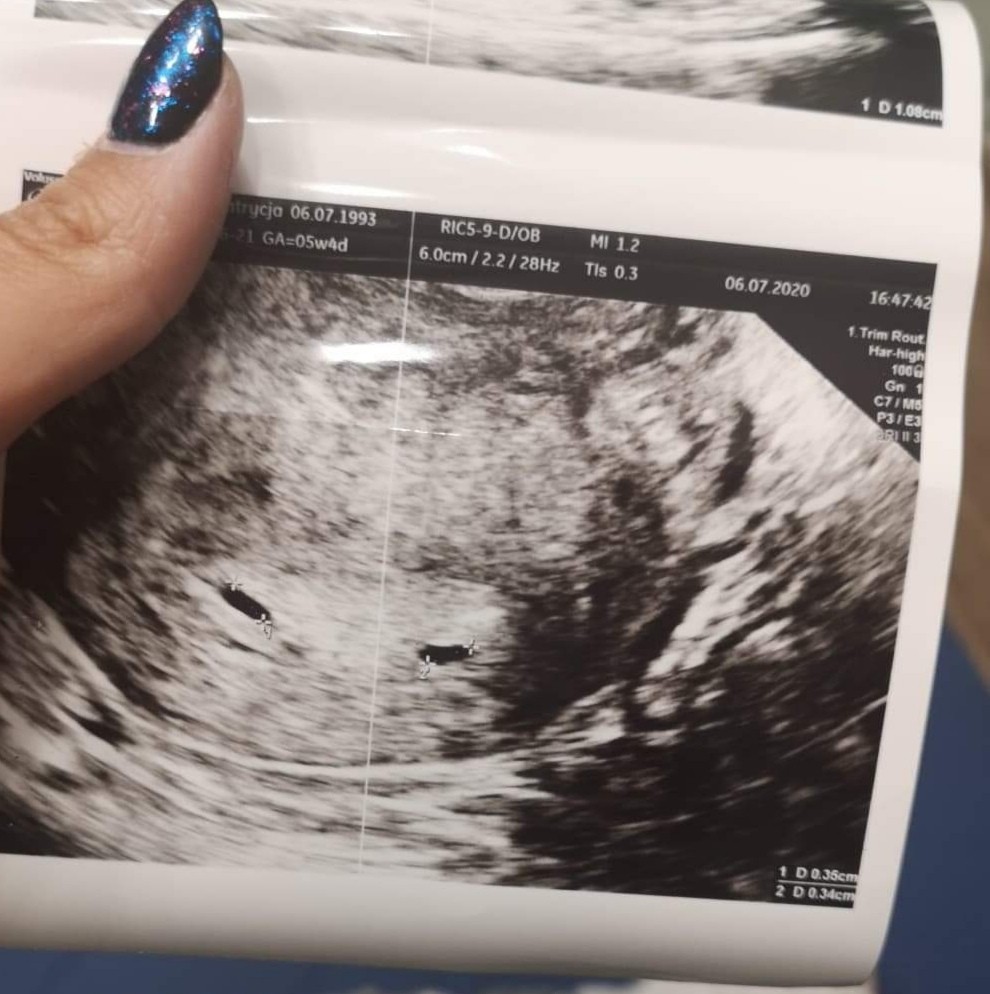

Byłam dziś na wizycie. Pani Doktor na USG dziś pokazala mi bijące serduszko w jednym pęcherzyku i drugi pęcherzyk bez serduszka tj 6ti 1 d ciąży. Powiedziała, że 4 lipca powie mi czy ciąża mnoga czy nie. Jestem zdezorientowana. Myślałam że temat bliźniaków mnie nie dotyczy. Nic nie wiem na ten temat. Ogólnie jestem po dwóch porodach. Jeden w 2016 roku- córka, i drugi w październiku 2019- syn. Obie ciążę wyczekane i wystaran, a teraz niespodzianka i być może podwójna. Boję się strasznie

Dziewczyny, owulacja 15 czerwca. Usg wczoraj. Czy nie uważacie, że pecherzyki są za małe?